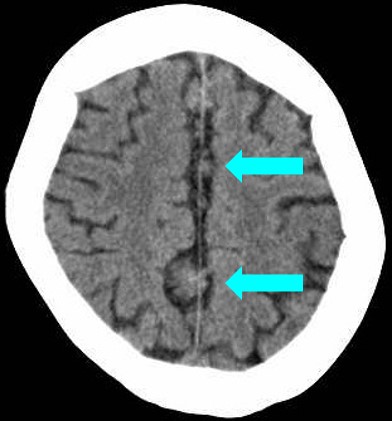

頭部CT・MRIにて、大脳鎌に沿った腫瘤を認め、左小脳橋角部にも腫瘤を認める。いずれもT1強調像で高信号、T2強調像で低信号を呈している。

頭部単純CT